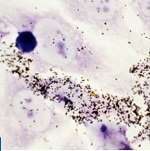

Le logiciel de traitement d'images développé au Groupe de recherche en informatique, image, automatisme et instrumentation de Caen identifie les cellules cancéreuses parmi les milliers de cellules présentes sur une seule lame de microscope. La start-up Datexim, inspirée par ces travaux lors de ses collaborations avec le laboratoire, a développé et commercialisé son logiciel CytoProcessorTM, en expérimentation au Centre hospitalier public du Cotentin, à Cherbourg.